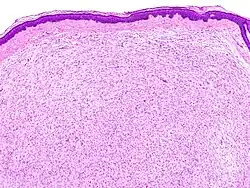

Neurofibrome sind Nerventumore, die innerhalb des Nervs gut abgrenzbare oder außerhalb des Nervs diffuse Strukturen ausbilden. Sie bestehen aus neoplastischen Schwann-Zellen, Fibroblasten und perineuralen Zellen, die in eine Matrix aus Kollagenfasern eingebettet sind. Sie werden auf der WHO-Skala von I-IV mit der Stufe I klassifiziert. Vom Schwannom unterscheiden sie sich durch einen höheren Gehalt an bindegewebiger Substanz und dadurch, dass sie operativ nicht von den Nerven getrennt werden können und diese in der Regel geopfert werden müssen.

Sie können als solitäre Knötchen praktisch überall, wo Nervengewebe vorhanden ist, auftreten. Am häufigsten treten sie auf der Haut auf. Multiples Auftreten beobachtet man insbesondere bei der Neurofibromatose Typ 1, diese ist auf eine Mutation im NF1-Gen zurückzuführen. Die plexiforme Variante tritt vorwiegend an größeren Nerven auf und es besteht bei dieser ein Entartungsrisiko zum malignen peripheren Nervenscheidentumor (MPNST). Das myxoide Neurofibrom ist typisch für das NAME-Syndrom.[1][2]